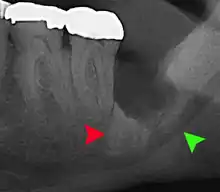

Impacted wisdom tooth with a backward tilt (distoangular impaction) and chronic infection to back of crown (green arrow)

Pericoronitis (green arrow) in lower right wisdom tooth

Impacted wisdom teeth without communication to the mouth, that have no pathology associated with the tooth, and have not caused tooth resorption on the blocking tooth, rarely have symptoms.[11] The chances of developing pathology on an impacted wisdom tooth that is not communicating with the mouth is approximately 12%.[11] However, when impacted wisdom teeth communicate with the mouth, food and bacteria penetrate to the space around the tooth and cause symptoms such as localized pain, swelling and bleeding of the tissue overlying the tooth. The tissue overlying the tooth is called the operculum, and the disorder is called pericoronitis which means inflammation around the crown of the tooth.[5]:141 Low grade chronic periodontitis commonly occurs on either the wisdom tooth or the second molar, causing less obvious symptoms such as bad breath and bleeding from the gums. The teeth can also remain asymptomatic (pain free), even with disease.[7]